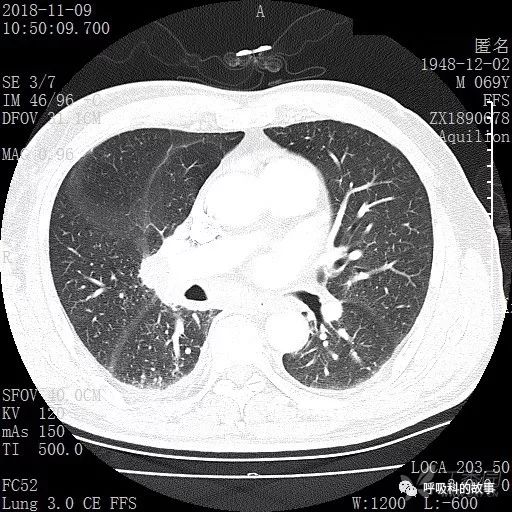

胸部增强CT示右肺门占位伴远端阻塞性肺炎,纵膈、右肺门、右侧颈根部、右侧腋下及肝门部肿大淋巴结。两侧胸腔少量积液。

纵隔窗的增强CT

肺窗CT